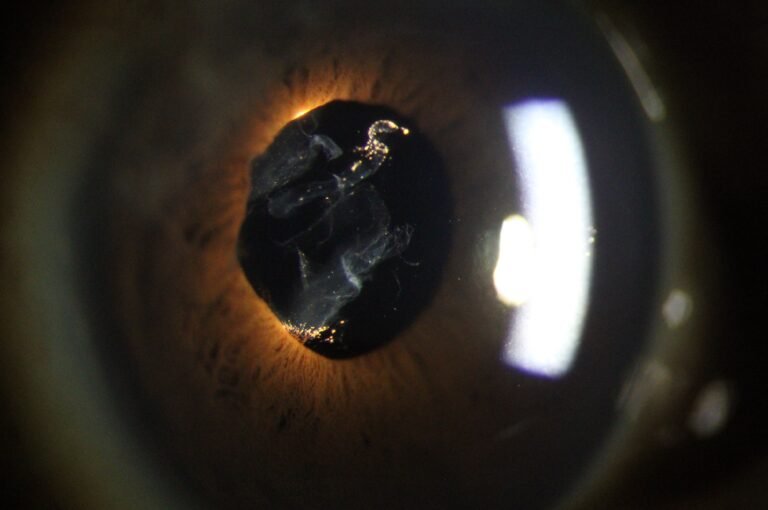

Integrated Filters

Built-in Yellow Filter

The PSL-9000 features a built-in yellow barrier filter that works in combination with cobalt blue illumination to reveal sodium fluorescein staining patterns on the cornea and ocular surface with exceptional clarity.

Precision Optics

Premium Optical System

High-resolution visualization across a wide range of magnifications. Multi-coated optics deliver distortion-free anterior segment imaging for confident clinical assessment.

- 5 Step Magnification: 6×, 10×, 16×, 25×, 40×

- 24 Megapixel SLR Camera

- Automatic Digital Optimization

- Automatic Eye Position Recognition for Digital Acquisition

Advanced Dry Eye analysis

Built-in Digital Analysis